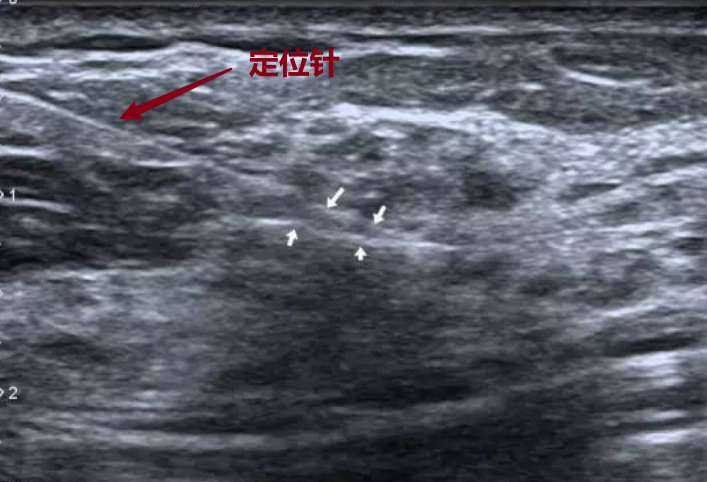

定位针置入结节内部

我们会在超声或钼靶引导下,确定定位的结节位置,然后置入定位针。

(B超引导下乳腺结节定位)